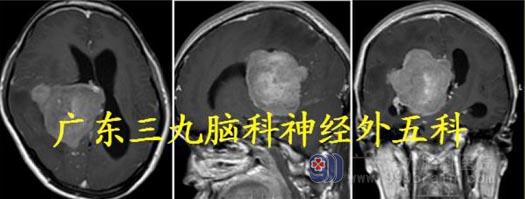

入院诊断:右侧侧脑室三角区占位:脑膜瘤?

头颅MR:右侧侧脑室三角区内团块状长T1 稍长T2 异常信号,FLAIR 序列呈稍高信号,增强后明显强化,范围约53.2mm×65.6mm×66.3mm,考虑脑膜瘤;合并幕上梗阻性脑积水;小脑扁桃体下疝;右侧大脑镰下疝。

头颅CTA:右侧侧脑室三角区巨大稍高密度占位性病变,血供丰富,主要由右侧大脑后动脉及脉络膜动脉供血。

术中见灰白色肿瘤组织,肿瘤质脆,血供丰富,边界清晰,于显微镜下用超吸行瘤内分块切除肿瘤,瘤内切除大部分肿瘤后逐步电凝分离肿瘤边缘,于侧脑室底肿瘤与脉络丛有粘连,电凝后切断,行显微镜下全切除。

术后MR 显示肿瘤彻底切除,术后病理:过渡型脑膜瘤WHO I 级。